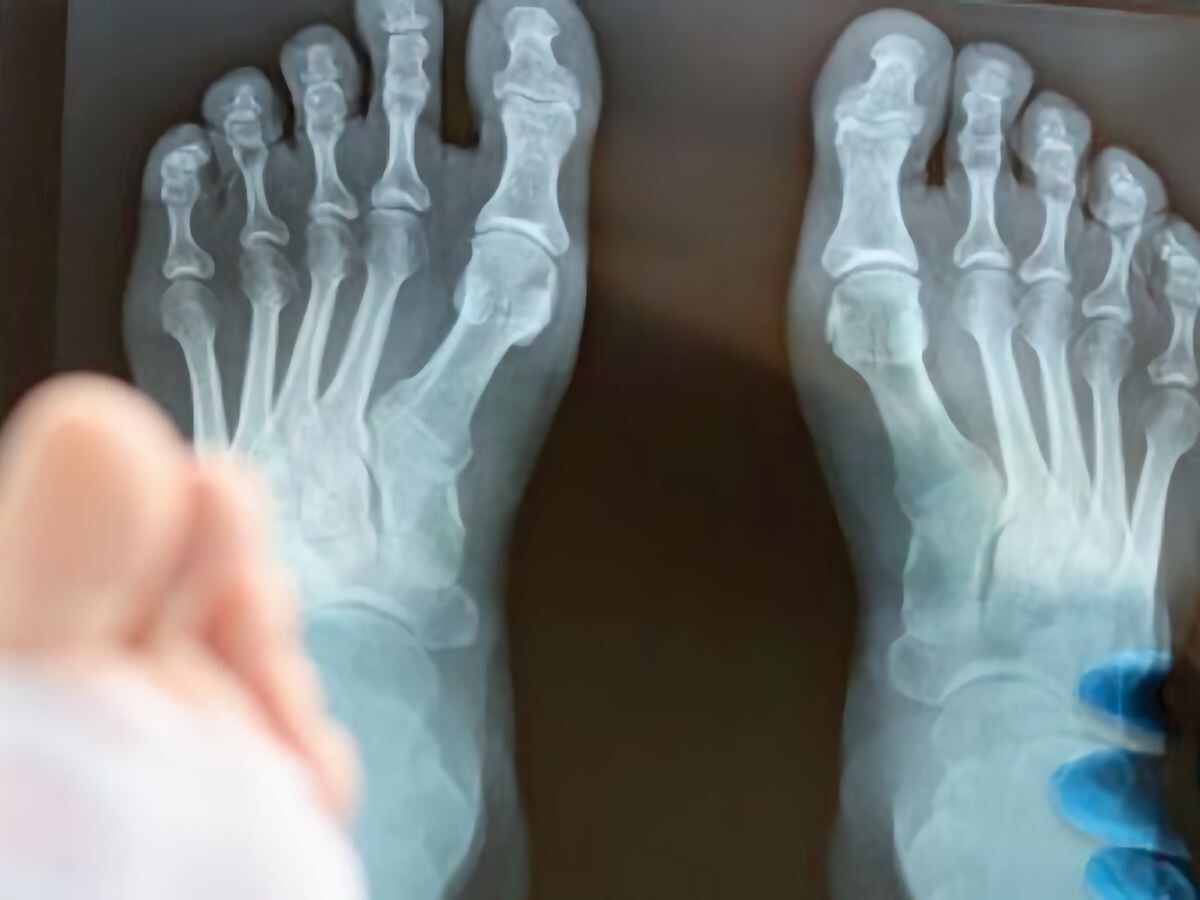

Учёные из Университета Цюриха разработали гидрогелевый имплантат, который может изменить подход к восстановлению костей. Новый материал на 97% состоит из воды и по консистенции напоминает желе, но при этом способен формировать прочные структуры, повторяющие внутреннюю архитектуру кости.

Традиционно при тяжёлых переломах и удалении костных опухолей врачи используют либо аутотрансплантаты (собственную кость пациента), либо металлические и керамические имплантаты. Первый вариант требует дополнительной операции, второй — слишком жёсткий по сравнению с естественной костью и со временем может расшатываться.

Новая разработка предлагает иной путь: вместо жёсткой «заплатки» — временную биосовместимую структуру, которая работает вместе с организмом. Гель можно «печатать» лазером с точностью до 500 нанометров — это тоньше человеческого волоса — и с рекордной скоростью до 400 мм/с.